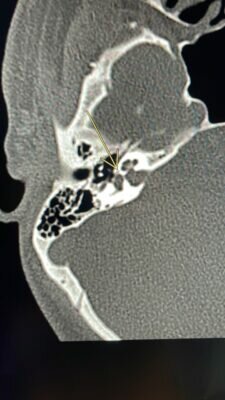

وأوضح رئيس الفريق الطبي المعالج الدكتور/ حاتم عبادة إستشاري جراحة التجميل والترميم وعلاج الحروق بالمستشفى ومدير خدمات جراحة التجميل بالتجمع الصحي بمكة أنه بعد معاينة المريض فى قسم الطوارئ تبين أنه يعاني من حروق عميقة من الدرجة الثانية والثالثة بنسبة ٩٠٪ من إجمالي مساحة سطح الجسم مع تأثر الجهاز التنفسي والرئتين بسبب إستنشاق الأدخنة والغازات فى موقع الحريق وعلى الفور بدأ الفريق الطبي المعالج تطبيق الخطة العلاجية بإنعاش المريض وتعويض الجسم بالسوائل والأملاح وتحسين الدورة الدموية وكذلك إعطائه العلاج اللازم من مسكنات ومضادات حيوية بعد تنويمه فى قسم الحروق بالمستشفى وفقاً لأحدث البروتوكولات الطبية المتبعة فى مثل هذه الحالات وبالتعاون مع التخصصات الأخرى مثل التغذية العلاجية والتأهيل الطبي والعلاج الطبيعي ومكافحة العدوى والخدمة الاجتماعية والتخدير والعمليات كل فيما يخصه. كما تم إخضاع المريض لعمليات جراحية لتغطية الحروق العميقة بإستخدام بدائل الجلد والرقع الجلدية المستخلصة من الأماكن السليمة القليلة المتبقية.